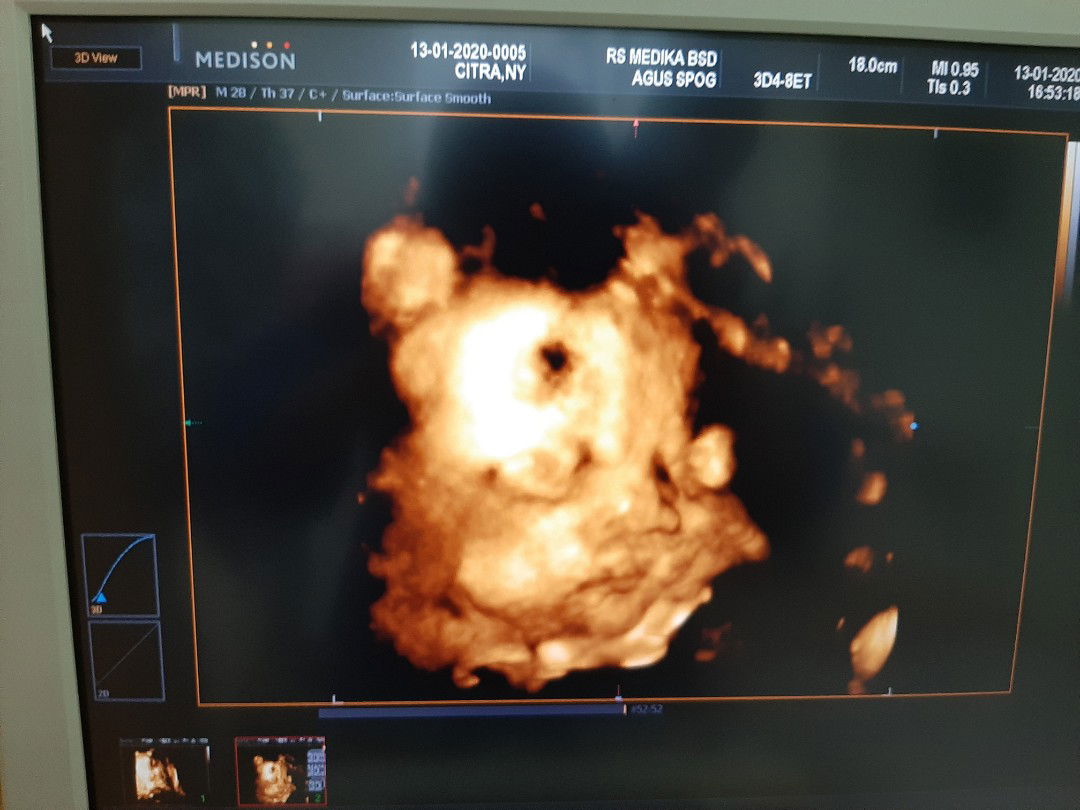

jagoan kecil

Sitembem..belum apa2 udh pingin gigit pipinya..??

Lucu nya bun masih di usg jga

Di usg aja udh lucu ya